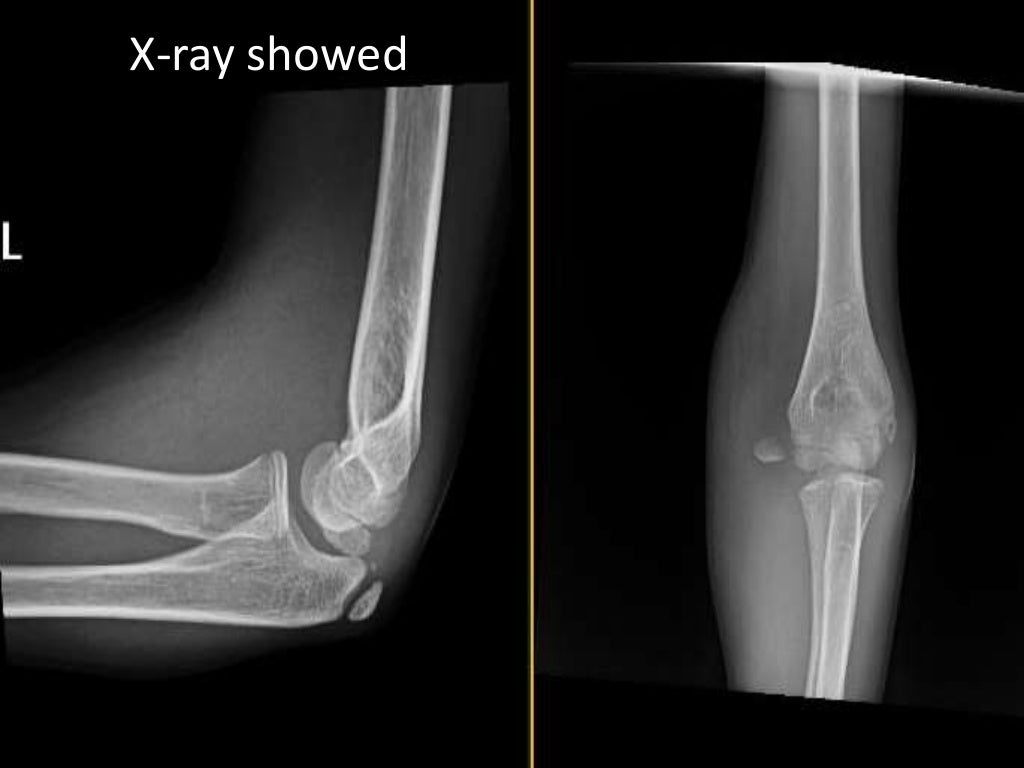

Initial Xray of the fracture of the medial epicondyle Download

Initial Xray of the fracture of the medial epicondyle Download Medial Epicondyle Fracture X Ray Medial epicondylar fractures are the third most common elbow fracture seen in children and are usually seen in boys between the ages of 9 and 14. Careful consideration of the other ossifications should. Undisplaced or minimally displaced fractures may be difficult to see on x. Avulsion fracture of the medial humeral epicondyle with adjacent soft tissue swelling. The medial epicondyle. Medial Epicondyle Fracture X Ray.